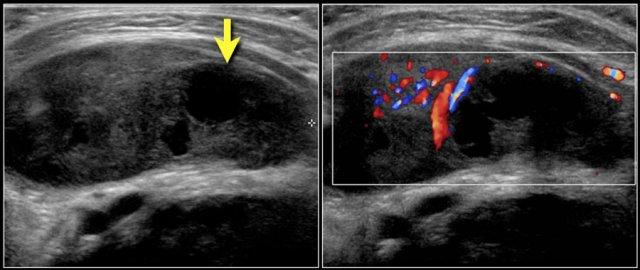

Video cho thấy một khối sưng xuất hiện qua đêm ở một bé gái 13 tuổi.

Một tổn thương giảm âm được nhìn thấy nằm nông so với động mạch cảnh và sâu so với cơ ức đòn chũm.

Không thấy sự di chuyển của nội dung tổn thương khi gõ nhẹ bằng đầu dò.

Khi bé gái được yêu cầu ngồi thẳng, nội dung bên trong xoáy chuyển động.